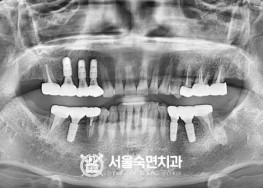

임플란트-치료-전후사진

서울대학교-출신-보건복지부-인증-통합치의학과-전문의-2인-책임관리